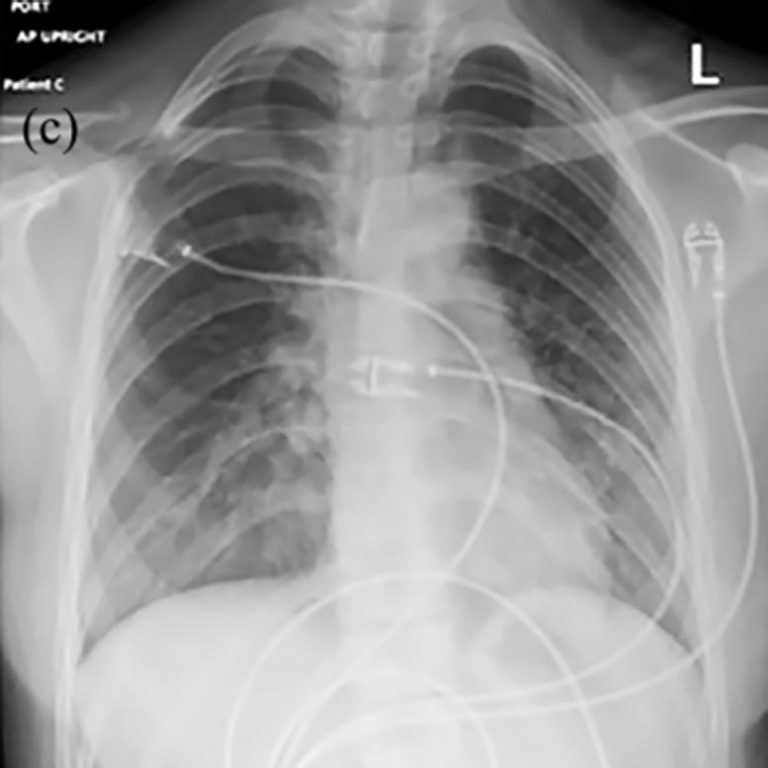

Do Chest X Rays Show Vaping . multivariable analyses were performed to test associations between age, sex, substance vaped, vaping frequency, vaping duration, and number of days since symptom onset with radiologic pattern and percentage of lung involved on ct scan as primary outcomes. The findings resemble increased pressure edema, but the heart size is normal. (a) posteroanterior radiograph shows midlung and lower lung consolidation and opacity bilaterally. chest radiology is the cornerstone of diagnosis and monitoring of evali. A wide variety of radiological findings highlight the need for standardisation of.